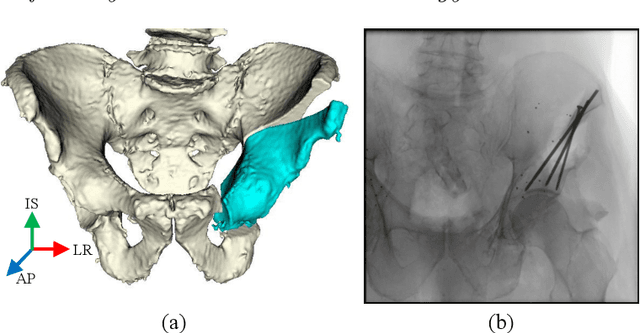

Abstract:Accurate and consistent mental interpretation of fluoroscopy to determine the position and orientation of acetabular bone fragments in 3D space is difficult. We propose a computer assisted approach that uses a single fluoroscopic view and quickly reports the pose of an acetabular fragment without any user input or initialization. Intraoperatively, but prior to any osteotomies, two constellations of metallic ball-bearings (BBs) are injected into the wing of a patient's ilium and lateral superior pubic ramus. One constellation is located on the expected acetabular fragment, and the other is located on the remaining, larger, pelvis fragment. The 3D locations of each BB are reconstructed using three fluoroscopic views and 2D/3D registrations to a preoperative CT scan of the pelvis. The relative pose of the fragment is established by estimating the movement of the two BB constellations using a single fluoroscopic view taken after osteotomy and fragment relocation. BB detection and inter-view correspondences are automatically computed throughout the processing pipeline. The proposed method was evaluated on a multitude of fluoroscopic images collected from six cadaveric surgeries performed bilaterally on three specimens. Mean fragment rotation error was 2.4 +/- 1.0 degrees, mean translation error was 2.1 +/- 0.6 mm, and mean 3D lateral center edge angle error was 1.0 +/- 0.5 degrees. The average runtime of the single-view pose estimation was 0.7 +/- 0.2 seconds. The proposed method demonstrates accuracy similar to other state of the art systems which require optical tracking systems or multiple-view 2D/3D registrations with manual input. The errors reported on fragment poses and lateral center edge angles are within the margins required for accurate intraoperative evaluation of femoral head coverage.